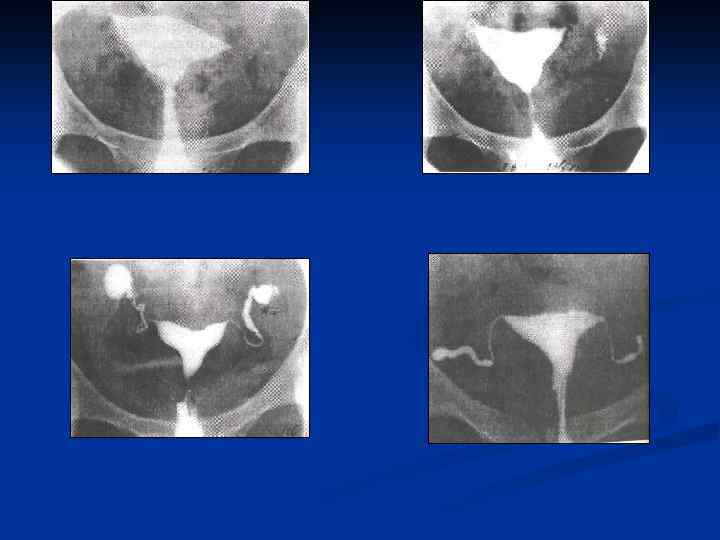

n n n Провести рентгеновское исследование грудной клетки, а если есть показания, то и других органов; Определить туберкулиновую чувствительность; Назначить и провести гистеросальпингографию с 60% раствором водорастворимого верографина, при этом возможно: n n n Определить состояние маточных труб (тонкие, ригидные, запаянные ампулярные отделы, деформация в виде четок, курительных трубок); Выявить форму полости матки, ее размеры, наличие или отсутствие сокращений; Диагностировать наличие / отсутствие рефлюкса контрастного вещества из труб.